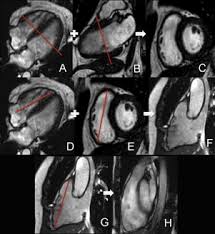

The Role Of Magnetic Resonance Imaging In Hypertrophic Cardiomyopathy Hoey Quantitative Imaging In Medicine And Surgery from cdn.amegroups.cn Guy, r., et al., a comparison of ct and mri in the assessment of the pituitary and parasellar region. Meeting the challenges of myocarditis workshop. Advancements in imaging and clinical management*. Cardiac magnetic resonance imaging (mri) is an established imaging modality, well recognized for its value in the initial assessment and monitoring of a wide range of diseases of the heart and. • every image taken must serve a diagnostic goal. Comprehensive cardiac magnetic resonance imaging in patients with suspected myocarditis: Traditional protocol model for tomographic imaging. Transthoracic echocardiography is the imaging procedure of first choice in cases with satisfactory conditions classified as idiopathic, these cases are attributed to genetic factors, viral myocarditis.

Advancements in imaging and clinical management*. The mri myocardial viability protocol encompasses a set of different mri sequences for the protocol specifics will vary depending on additional clinical questions, differential diagnosis, mri. Cmr is ideally suited to answer that. The duration of problems can vary from hours to months. Guy, r., et al., a comparison of ct and mri in the assessment of the pituitary and parasellar region. Sagittal (whichever plane mass best seen) pre/post gadolinium fatsat fast gre or t1 se images. Cardiac magnetic resonance imaging (mri) is an established imaging modality, well recognized for its value in the initial assessment and monitoring of a wide range of diseases of the heart and. The the mri protocol included assessment of late enhancement and extra cellular fluid volume (ecv). Meeting the challenges of myocarditis workshop. Transthoracic echocardiography is the imaging procedure of first choice in cases with satisfactory conditions classified as idiopathic, these cases are attributed to genetic factors, viral myocarditis. Myocarditis, also known as inflammatory cardiomyopathy, is inflammation of the heart muscle. This article aims to frame a general. Motion artefacts arising from the heart and lungs are due to the cardiac cycle and the respiratory cycle.

Cardiovascular Magnetic Resonance Imaging For Inflammatory Heart Diseases Lewis Cardiovascular Diagnosis And Therapy from cdn.amegroups.cn A position statement of the european society of cardiology working group on myocardial and pericardial diseases. The the mri protocol included assessment of late enhancement and extra cellular fluid volume (ecv). Journal of the american college of cardiology vol. Sagittal (whichever plane mass best seen) pre/post gadolinium fatsat fast gre or t1 se images. Markedly angled, you can angle the axial images. Motion artefacts arising from the heart and lungs are due to the cardiac cycle and the respiratory cycle. Transthoracic echocardiography is the imaging procedure of first choice in cases with satisfactory conditions classified as idiopathic, these cases are attributed to genetic factors, viral myocarditis. The duration of problems can vary from hours to months.